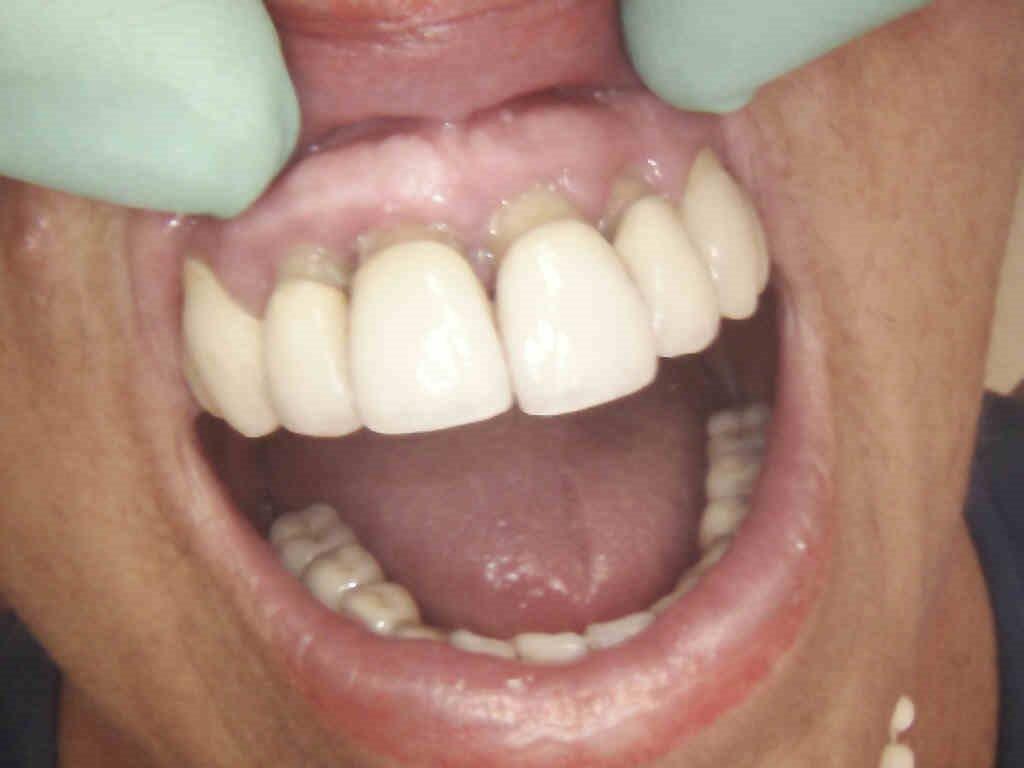

4 – Inserimento impianti e ricostruzione ossea zona incisivi superiori